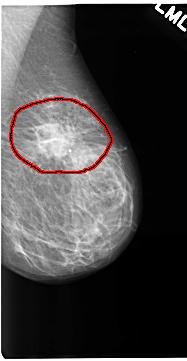

C_0123_1.LEFT_MLO

FILE: C_0123_1.LEFT_MLO.OVERLAY

TOTAL_ABNORMALITIES 1

ABNORMALITY 1

LESION_TYPE MASS SHAPE IRREGULAR MARGINS ILL_DEFINED

ASSESSMENT 5

SUBTLETY 5

PATHOLOGY MALIGNANT

TOTAL_OUTLINES 1

BOUNDARY